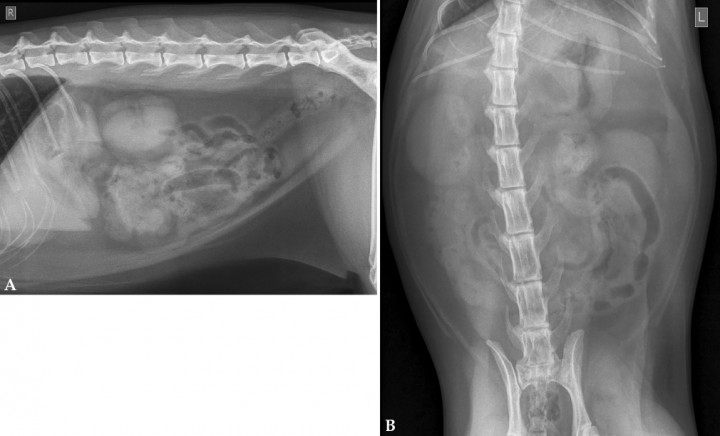

Se presentó en consulta de urgencias un gato Común Europeo, macho castrado, de 10 años y 6,5 kg de peso. El motivo de la consulta fue que había presentado tres vómitos biliosos desde la noche anterior, hiporexia, apatía y habían encontrado un fragmento de hilo en las heces. En la exploración física se apreció una ligera deshidratación y dolor a la palpación abdominal. No se detectaron alteraciones relevantes en las analíticas sanguíneas. Se realizaron radiografías de la cavidad abdominal en proyecciones lateral derecha (Fig. 1A) y ventrodorsal (Fig. 1B).

<p>Radiografías de la cavidad abdominal de un gato Común Europeo de 10 años. (<strong>A</strong>) Proyección lateral derecha. (<strong>B</strong>) Proyección ventrodorsal.</p>

Radiografías de la cavidad abdominal de un gato Común Europeo de 10 años. (A) Proyección lateral derecha. (B) Proyección ventrodorsal.